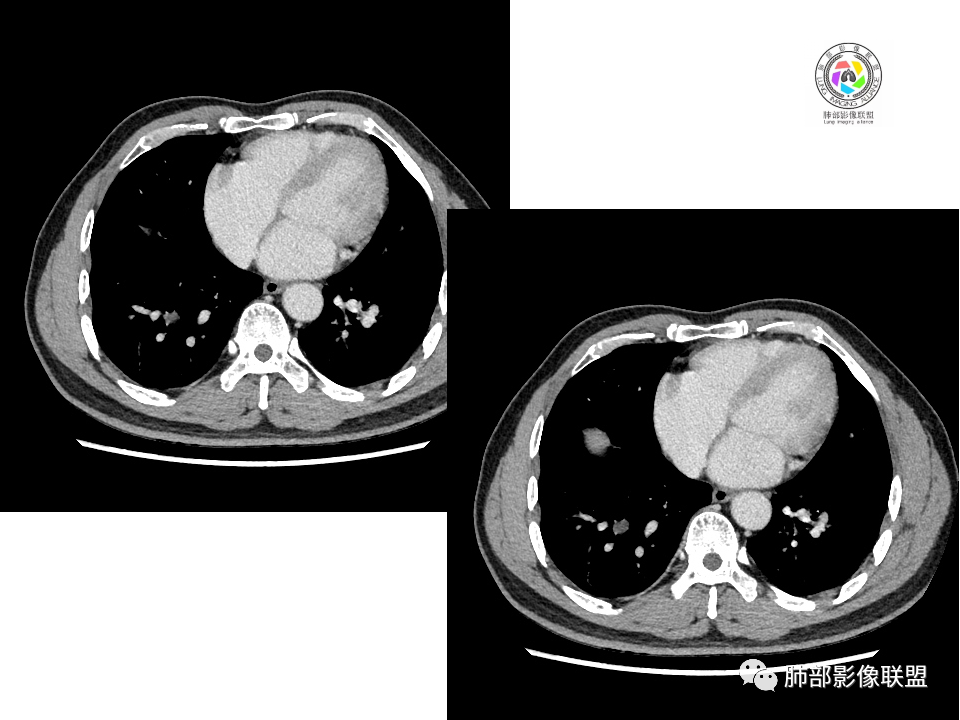

右肺中叶病灶

GGO,与支气管关系密切

这个形态、与支气管关系,与前两个不一致,所以考虑独立炎性病变。

3.右肺中叶外侧段胸膜下散在小片影,磨玻璃密度为主,边界不清,支气管相关。符合炎性特征!

5.慢性感染灶。缺乏临床表现,强化不显著会想到继发性肺结核,背段病灶过于光整均匀,周边过于干净使人狐疑,且“成掎角之势”的中叶病灶结核灶特点也着实不多。

有老师分析,多发病灶有磨玻璃晕,可以符合隐球菌感染,确实如此。但背段边缘如此锐利的块影还是更容易让人联想到新生物。

1、普通人隐球菌感染的时相:初期的隐球菌感染周围有晕,晕从多变少,或包裹,或吸收,结节实性区可迅速变大。后期(慢性期)的隐球菌周围无明显晕征,边界较清楚。

3、卫星灶与“蘑菇兄弟”:诊断隐球菌时,建议找卫星灶,卫星灶可以在遥远的地方。可以是遥远地方的微小结节——“小蘑菇兄弟”。有些远处的卫星灶,通常是不规则饱满实性的,晕征不明显。隐球菌的卫星灶非常“隐”,但发现率高达60%多,诊断价值高。

5、周围毛刺纤维、边缘形态等:坏死包裹会使得结节变圆;结节多缺乏明显的分叶征,缺乏局部突出生长能力;如果出现分叶,是由多处肉芽肿中心形成。没有坏死的局限化,结节只是凑合在一起,常呈方形征;毛刺进入晕区(概念源自南边老师),毛刺较短、较软;周围的晕吸收后,会留下不规则边,外面常残留丝状条索;收缩力较弱,临近胸膜对胸膜牵拉不明显。